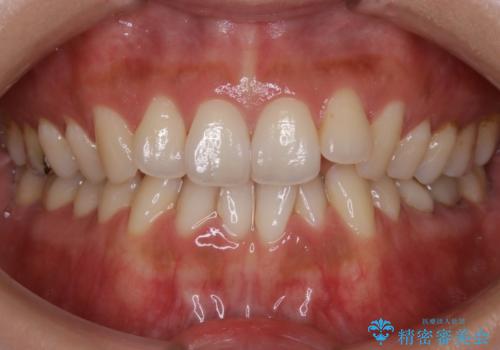

- 歯のガタつきによる見栄えや清掃困難を主訴にご来院されました。

左側の噛み合わせは上の歯が前方に寄ってきてしまっていることが原因のズレがありました。

ガタつき自体は歯列の幅の拡大やディスキング(IPR)でほとんど解消可能でしたが、噛み合わせのズレは歯の移動が必要だったため、左上にマイクロインプラントを使用し噛み合わせの改善とガタつきの解消を同時に進めるという方針をとりました。